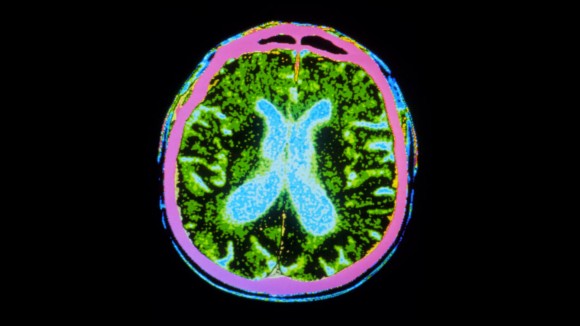

New York City, New York, Amerika Serikat - Jutaan sel punca disuntikkan ke otak orang dengan penyakit Parkinson sebagai bagian dari uji coba keamanan. Uji coba ini bertujuan untuk menggantikan sel-sel penghasil dopamin yang mati pada penderita Parkinson. Hasil awal menunjukkan bahwa terapi ini aman dan beberapa peserta mengalami pengurangan tremor yang terlihat.

Uji coba ini dilakukan di Amerika Serikat, Kanada, dan Jepang dengan melibatkan total 19 peserta. Sel punca yang digunakan berasal dari embrio manusia yang didonasikan dan sel dewasa yang dikembalikan ke keadaan pluripoten. Sel-sel ini kemudian disuntikkan ke putamen, struktur otak yang penting untuk fungsi motorik.